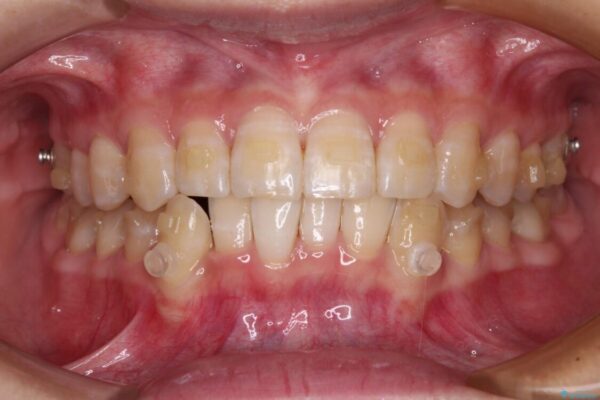

治療途中

• 【モニター】下顎前歯のデコボコをインビザラインできれいに 治療途中画像